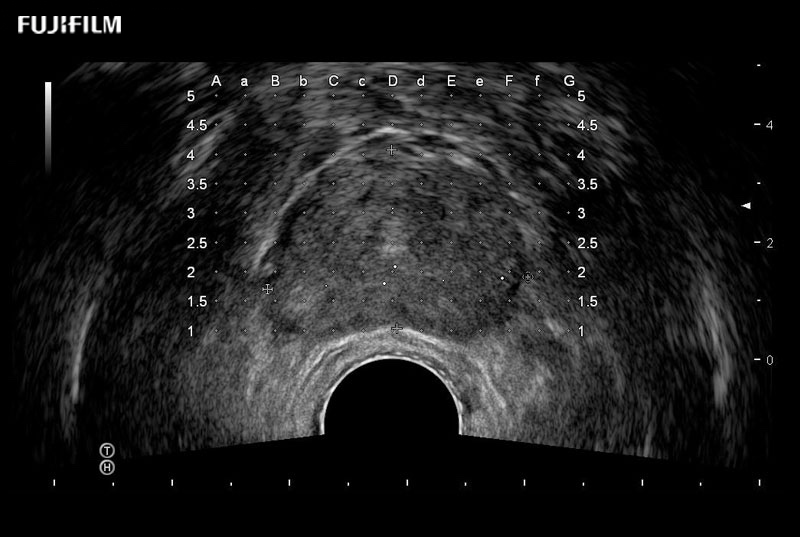

Exclusive 200° FOV end-fire prostate biopsy transducer.

Main Specifications:

Provides real-time imaging of both the sagittal and transverse planes